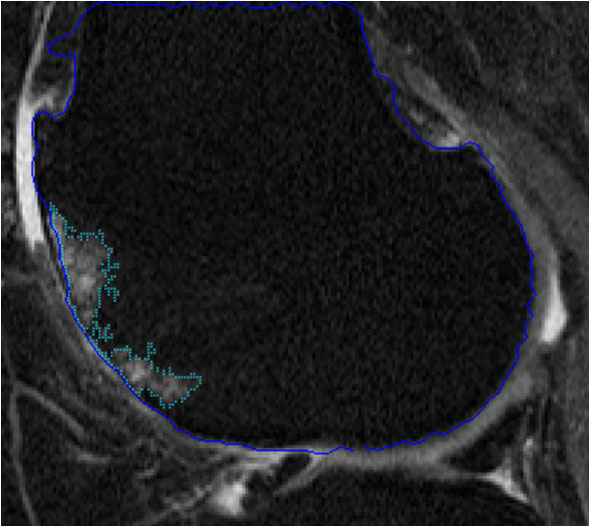

Bone marrow lesion volume

The majority of the work during the past five years has been supported by a successful NIH grant. (R01AR056664). The goal of this study was to develop and validate several software-based measures of knee OA from MRI data sets. Much of the group’s recent effort has been directed at accomplishing the aims of this grant proposal. We now have fast quantitative methods in place for cartilage morphometry (1-2), bone marrow lesion (BML) (3), and osteophyte volume (4), and have looked at associations of these measures with pain. Methods are in place to assess large numbers (several hundred) subjects for multiple disease-related structures, which will facilitate future higher power studies of knee OA. We are actively seeking additional funding to support the next phase of the program.